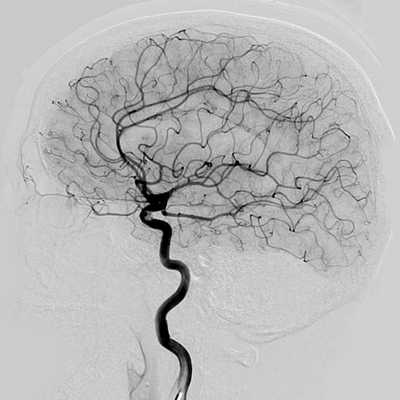

В каких случаях проводят ангиографию сосудов мозга при аневризме

- Позволяет визуализировать только свободный просвет, но не тромбированные участки.

- Дифференциация с помощью ДСА

- Кроме того, может быть показана ЗDротационная ангиография

- Ангиографию. Церебральная ангиография позволяет установить расположение, форму и размеры аневризмы. В отличие от рентгенологической ангиографии магнитно-резонансная (МРА) не требует введения контрастных веществ и может проводиться даже в остром периоде разрыва аневризмы сосудов головного мозга. Она дает двухмерное изображение поперечного сечения сосудов или их объемное трехмерное изображение.